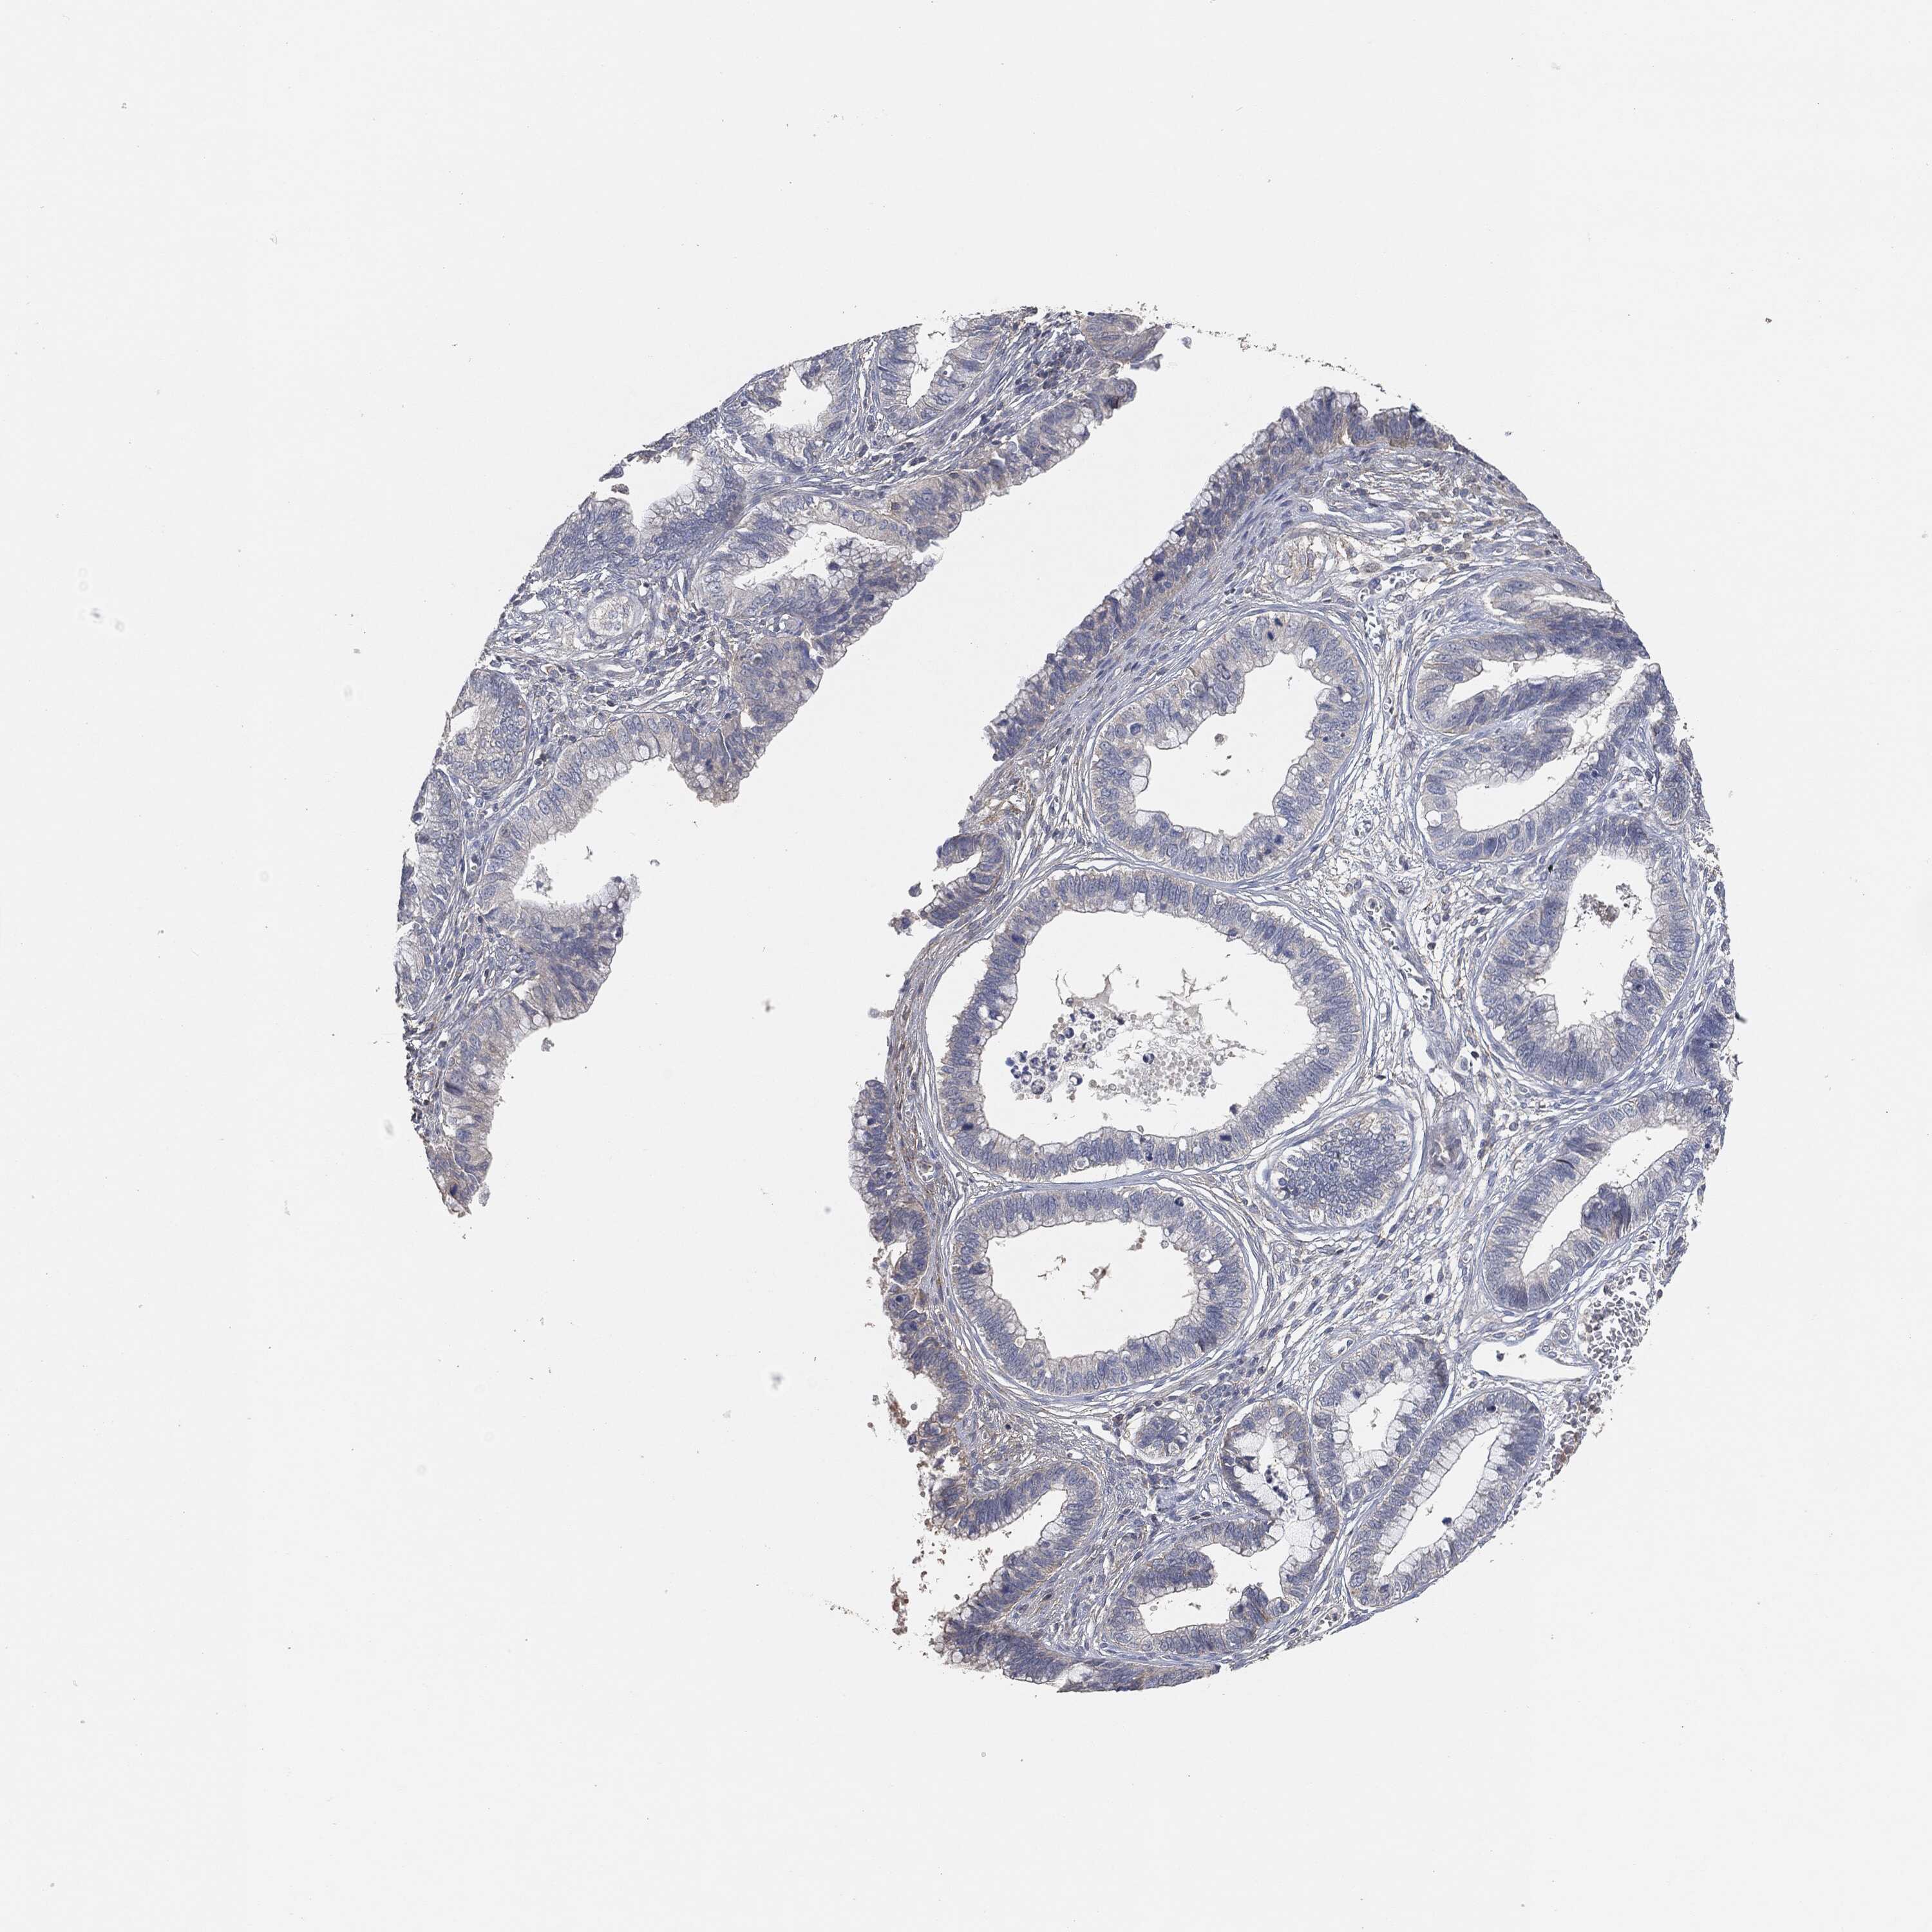

CERVICAL CANCER - Protein expressioni

A mouse-over function shows sample information and annotation data. Click on an image to view it in a full screen mode. Samples can be filtered based on level of antibody staining by selecting one or several of the following categories: high, medium, low and not detected. The assay and annotation is described here.

Note that samples used for immunohistochemistry by the Human Protein Atlas do not correspond to samples in the TCGA dataset.

Antibody stainingi

Antibody staining in the annotated cell types in the current human tissue is reported as not detected, low, medium, or high, based on conventional immunohistochemistry profiling in selected tissues. This score is based on the combination of the staining intensity and fraction of stained cells.

Each image is clickable and will lead to virtual microscopy that enables deeper exploration of all samples and also displays staining intensity scores, fraction scores and subcellular localization as well as patient and tissue information for each sample.

Staining

High

Medium

Low

Not detected

Intensity

Strong

Moderate

Weak

Negative

Quantity

>75%

75%-25%

<25%

None

Location

Nuclear

Cytoplasmic/membranous

Cytoplasmic/membranous,nuclear

Adenocarcinoma, NOS

Squamous cell carcinoma, NOS